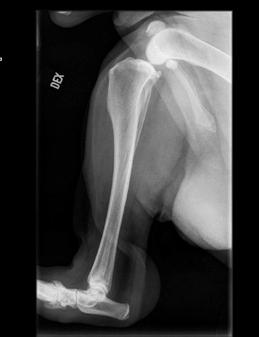

Epäilys osteosarkoomasta - miten edetä? Kliininen epäily OS:sta syntyy usein jo esitietojen ja yleistutkimuksen perustella - tyypillisin potilas on isokokoinen ontuva koira, jolla on putkiluun päässä aristava kyhmy. Röntgenkuvissa todetaan aggressiiviselle luustomuutokselle tyypilliset löydökset; luun syöpymää,

Kuva 2. Terve oikea sääriluu (a), jossa luun pinta on ehjä ja tasainen. Samalla koiralla todettiin osteosarkooma vasemman sääriluun alaosassa (b), jossa näkyy kasvaimen lisäksi voimakasta uudisluumuodostusta on todettavissa. Kuva: Evidensia Eläinsairaala Tammisto. Kuva 3. Röntgenkuva 6-vuotiaan bernhardinkoiran vasemman etujalan värttinäluun alaosan osteosarkoomasta. Alueella näkyy voimakasta uudisluumuodostusta ja luun normaali rakenne on tuhoutunut. Muutos ei kuitenkaan ylitä niveltä. Kuva: Evidensia Eläinsairaala Tammisto.

uudisluumuodostusta, luun normaali rakenne on tuhoutunut ja ympärillä on pehmytkudosturvotusta. (Kuvat 2a ja 2b, Kuva 3).